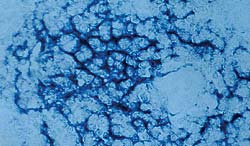

Technique "d'hybridation in situ" - Ganglion inguinal superficiel.

Présence de génome de PCV2 dans le cytoplasme des cellules d'aspect dendritique |